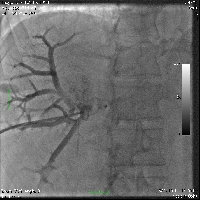

Πρόκειται για άνδρα ασθενή 50 ετών που υποβλήθηκε σε υπέρηχο άνω κοιλίας στα πλαίσια προληπτικού ελέγχου, ο οποίος ανέδειξε ογκόμορφη εξεργασία του ήπατος. Ακολούθησε αξονική τομογραφία, κατά την οποία διαπιστώθηκε μάζα μεγέθους 7 εκατοστών στα ηπατικά τμήματα 4a, 5 και 8 (εικόνα 1) που διηθούσε τη δεξιά και τη μέση ηπατική φλέβα. Επιπλέον, ανιχνεύθηκαν υψηλά επίπεδα α-Fp. Τέθηκε η διάγνωση του ηπατοκυτταρικού καρκινώματος σε έδαφος φυσιολογικού ηπατικού παρεγχύματος. Η ογκομέτρηση των τμημάτων 1, 2 και 3 ανέδειξε προβλεπόμενο σχετικό όγκο ηπατικού υπολείμματος 13,5%. Ο ασθενής υποβλήθηκε σε δεξιό πυλαίο εμβολισμό (εικόνα 2). Τέσσερεις εβδομάδες αργότερα, υποβλήθηκε σε ανάλυση MEVIS, σύμφωνα με την οποία αποφασίστηκε η διενέργεια δεξιάς εκτεταμένης (parenchymal sparing, anterior approach) ηπατεκτομής με προβλεπόμενο σχετικό όγκο ηπατικού υπολείμματος 37,2%. Πέντε εβδομάδες μετά τον πυλαίο εμβολισμό, ο ασθενής υποβλήθηκε στην προαναφερόμενη ηπατεκτομή (εικόνες 4, 5). Έλαβε εξιτήριο την 7η μετεγχειρητική ημέρα. Στην εικόνα 6 παρουσιάζεται το αναγεννώμενο ηπατικό υπόλειμμα, 15 ημέρες μετά την επέμβαση.